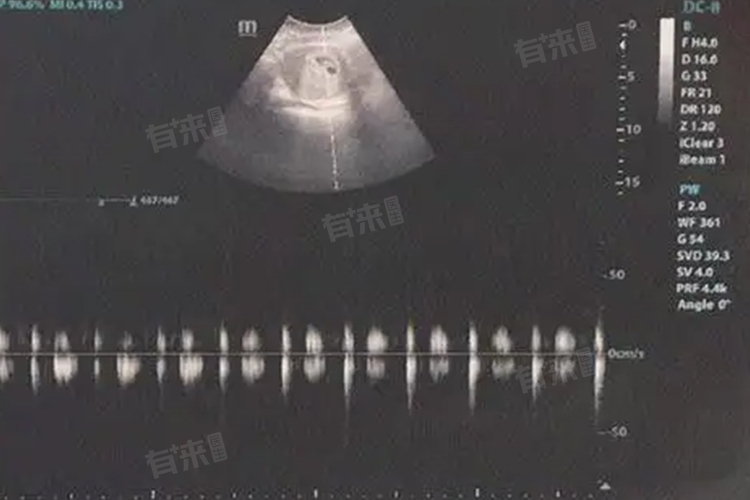

- 心管搏动出现于胚胎发育的极早期阶段。当胚胎发育至一定程度,原始心血管系统逐步成型,最初呈现为简单的管状结构。伴随着胚胎持续生长,这条心管便开始有节律地跳动,这便是心管搏动。一般在怀孕6-8周,借助超声检查手段,便能清晰观测到心管搏动现象。它代表胚胎心血管系统已开启工作,是早期胚胎存活与发育的关键证据。

- 胎心则有着更为严格的界定,在胚胎发育进程里,心脏逐步从简单的管状结构,历经复杂演变,发育出完整的心房、心室等心脏结构,具备完善的心脏形态与功能。此时,心脏所产生的有规律跳动,才被称为胎心。胎心是胎儿生命体征的核心指标,其跳动情况直观反映胎儿在母体内的健康程度。通常在怀孕8周之后,心管完成向完整心脏结构的转变,自此,我们能更精准地将其跳动描述为胎心搏动。随着胎儿发育,胎心的跳动频率与节律愈发稳定,趋于成熟。

1、定期产检:按时进行产前检查,通过胎心监护、超声检查等手段监测胎儿的胎心率和发育情况。正常胎心率为每分钟110-160次。